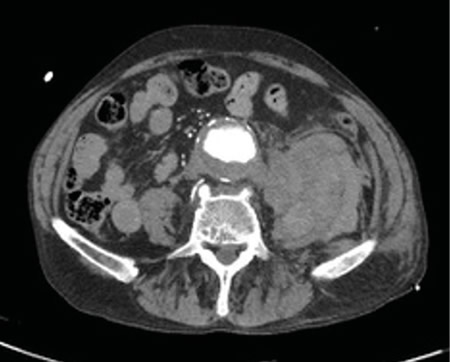

Figura 1